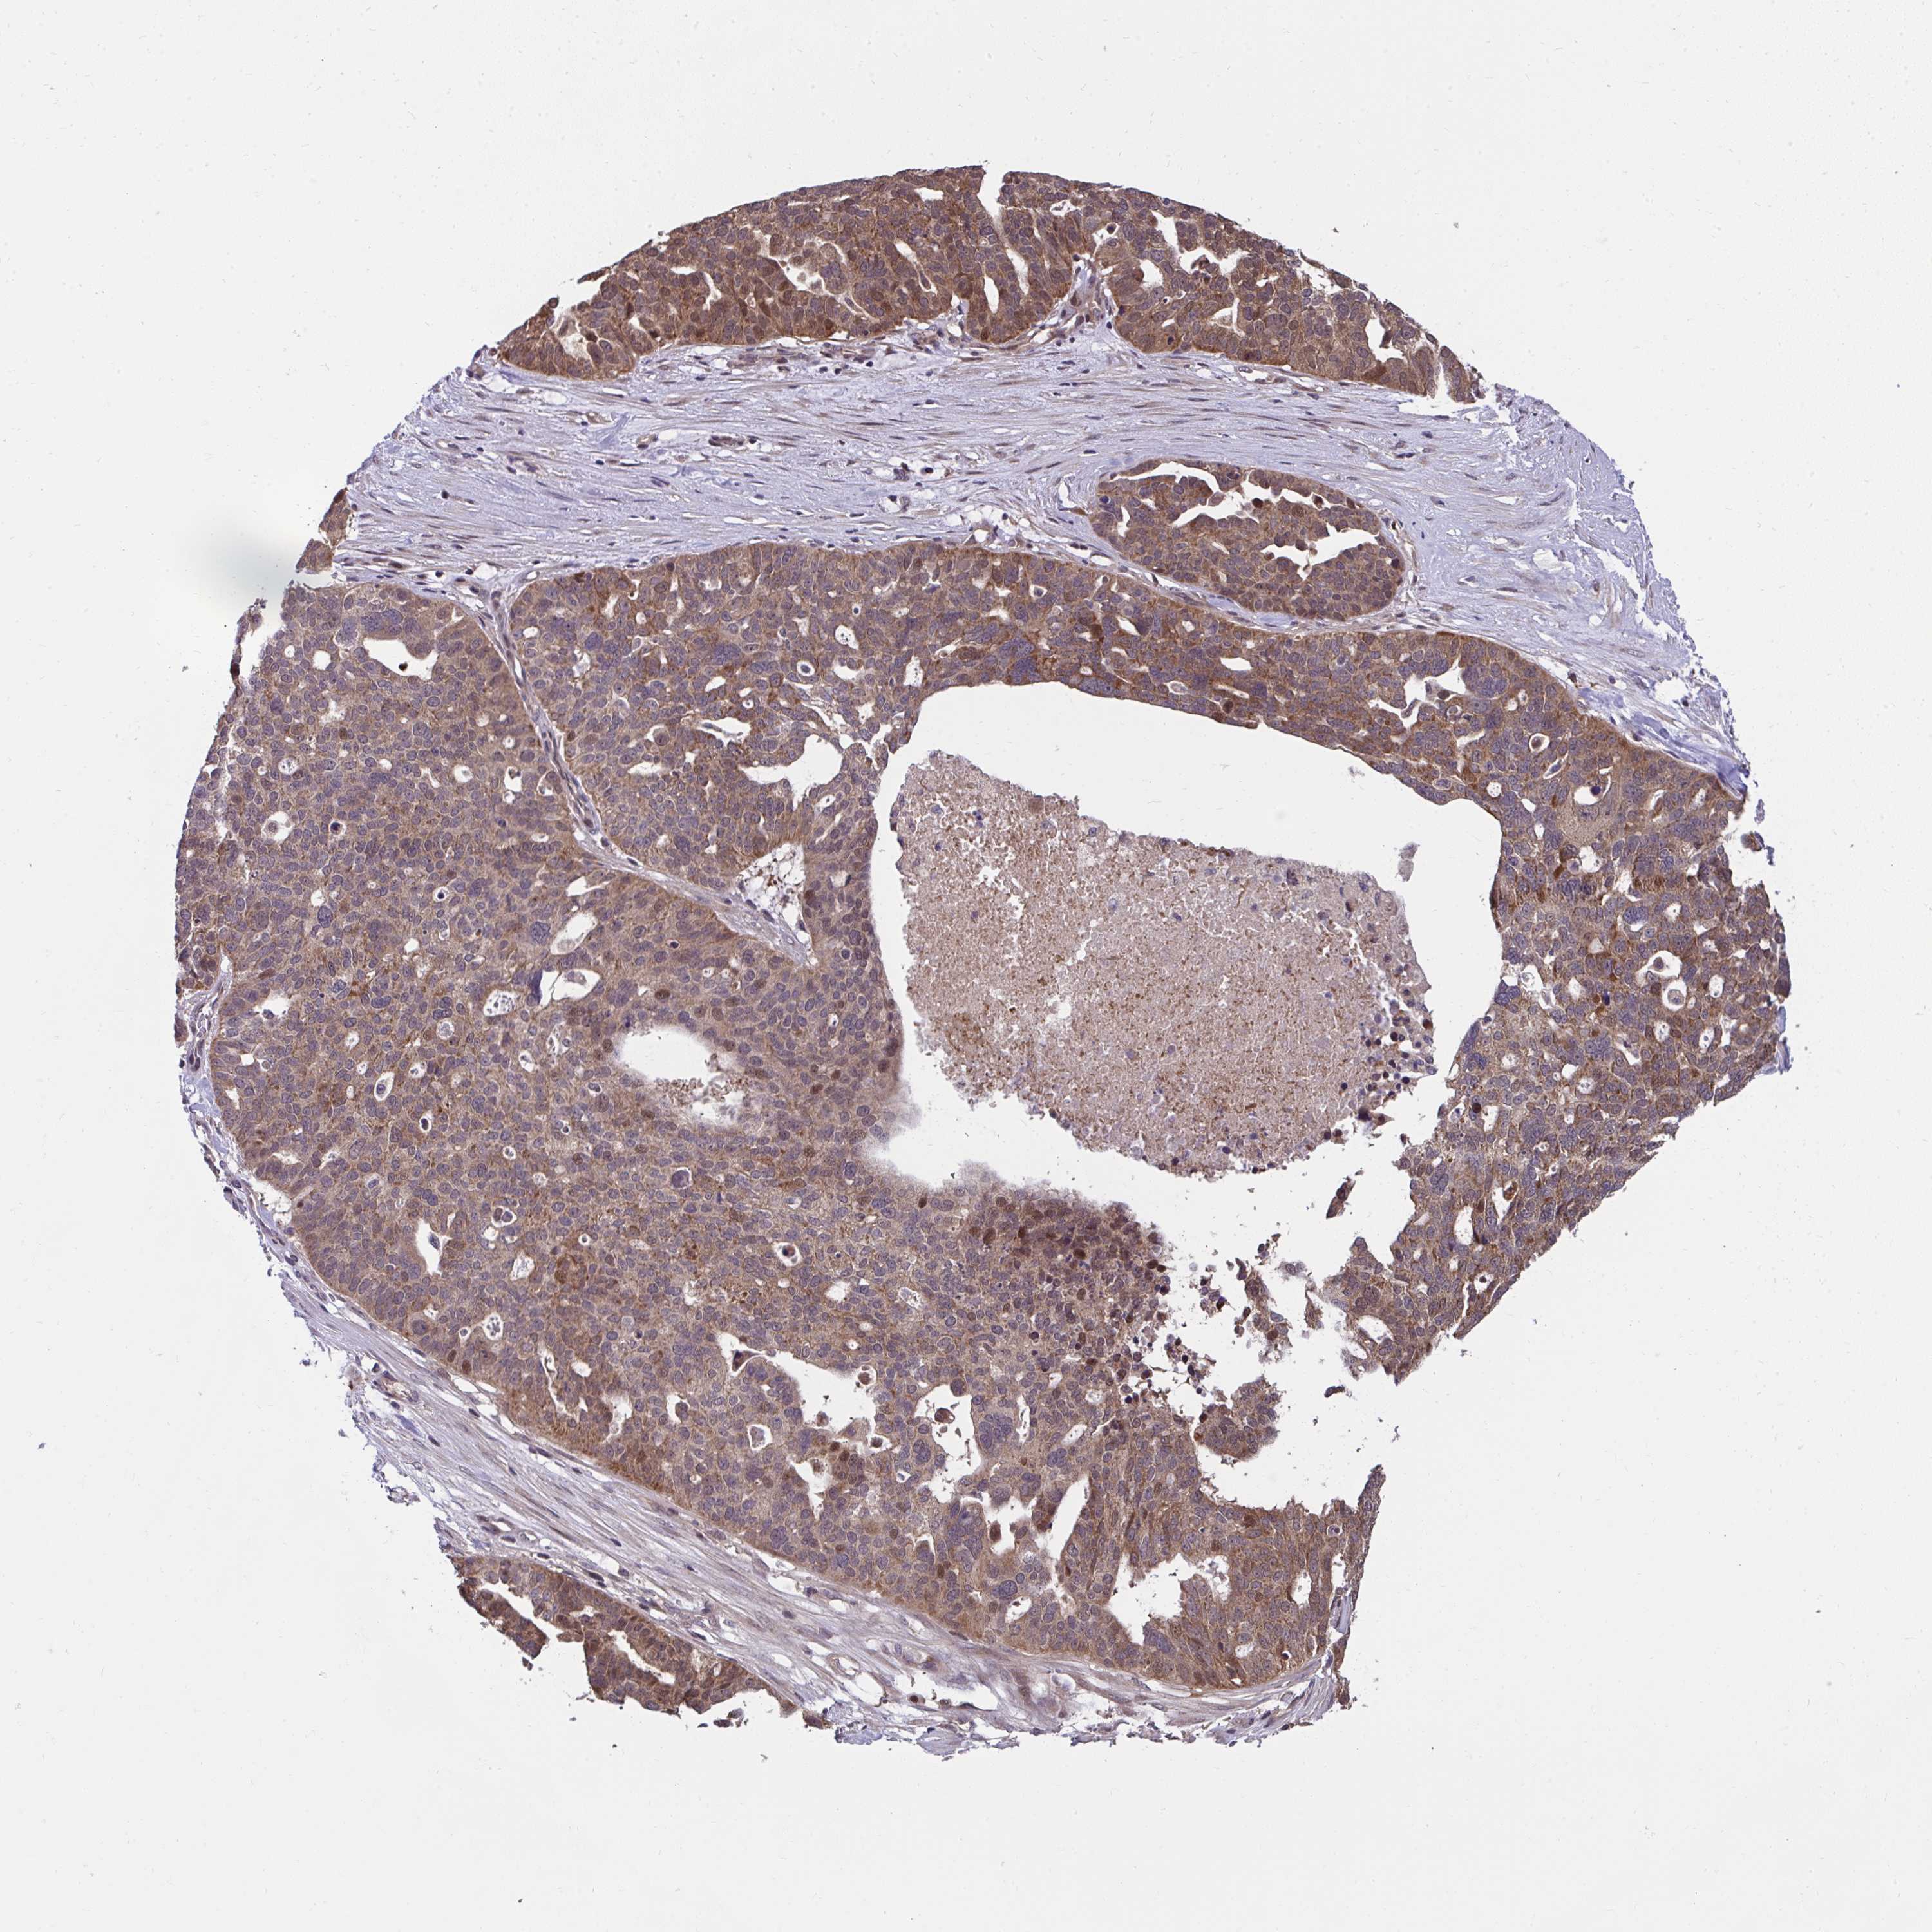

OVARIAN CANCER - Protein expressioni

A mouse-over function shows sample information and annotation data. Click on an image to view it in a full screen mode. Samples can be filtered based on level of antibody staining by selecting one or several of the following categories: high, medium, low and not detected. The assay and annotation is described here.

Note that samples used for immunohistochemistry by the Human Protein Atlas do not correspond to samples in the TCGA dataset.

Antibody stainingi

Antibody staining in the annotated cell types in the current human tissue is reported as not detected, low, medium, or high, based on conventional immunohistochemistry profiling in selected tissues. This score is based on the combination of the staining intensity and fraction of stained cells.

Each image is clickable and will lead to virtual microscopy that enables deeper exploration of all samples and also displays staining intensity scores, fraction scores and subcellular localization as well as patient and tissue information for each sample.

Antibody HPA056686

Staining

High

Medium

Low

Not detected

Intensity

Strong

Moderate

Weak

Negative

Quantity

>75%

75%-25%

<25%

None

Location

Nuclear

Cytoplasmic/membranous

Cytoplasmic/membranous,nuclear

Cystadenocarcinoma, serous, NOS

Carcinoma, endometroid

Cystadenocarcinoma, mucinous, NOS

Carcinoma, NOS